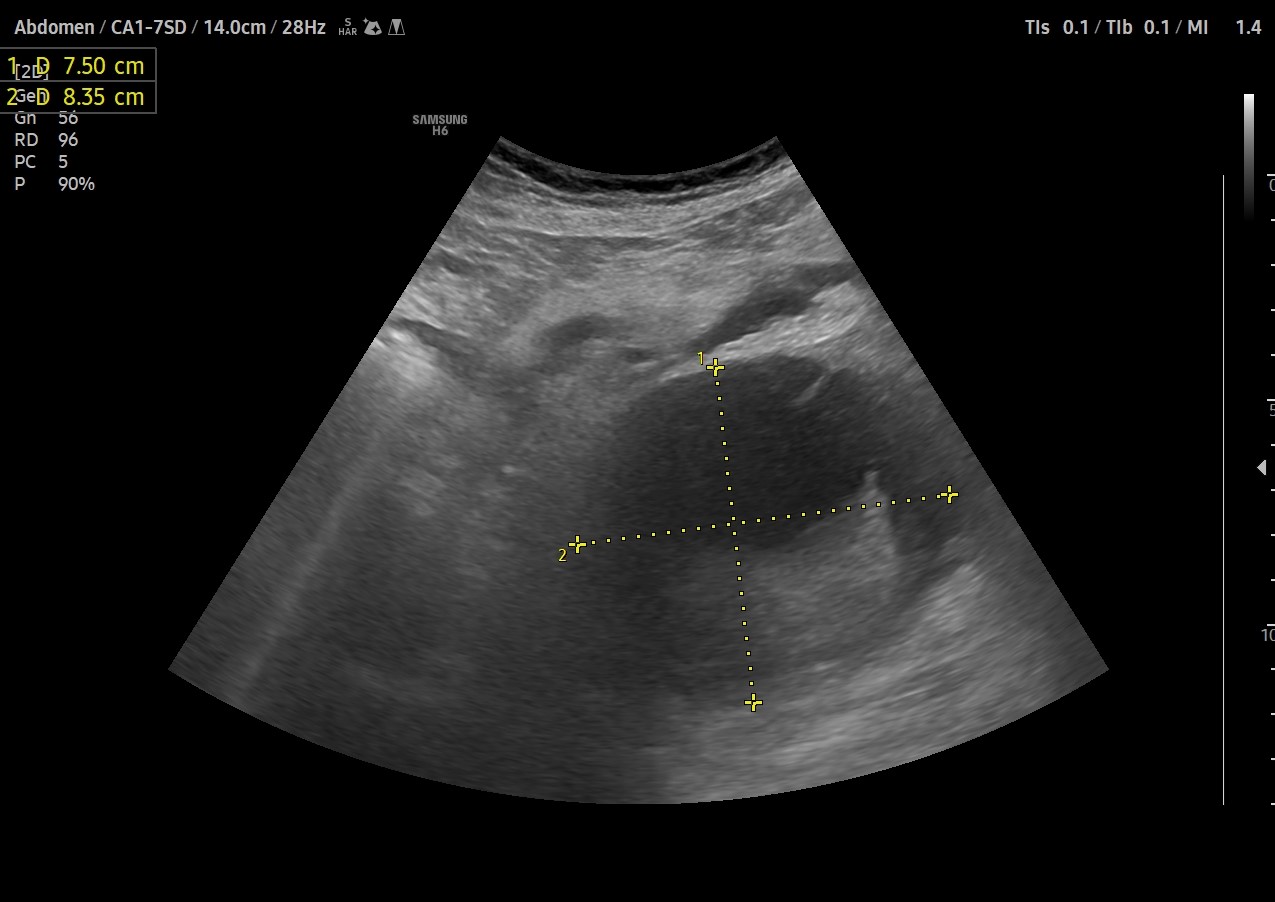

Dada la clínica y la afectacion del estado general se realiza ecografía clínica.

Hallazgos ecográficos

Se objetiva en HI masa bien delimitada de aprox. 8x8cm,que no parece tener relación con riñón izquierdo ni con el bazo,situado entre ambas estructuras,visible también a nivel de mesogastrio, de caracteristicas sólido-quísticas, inmóvil, sin captación de Doppler.